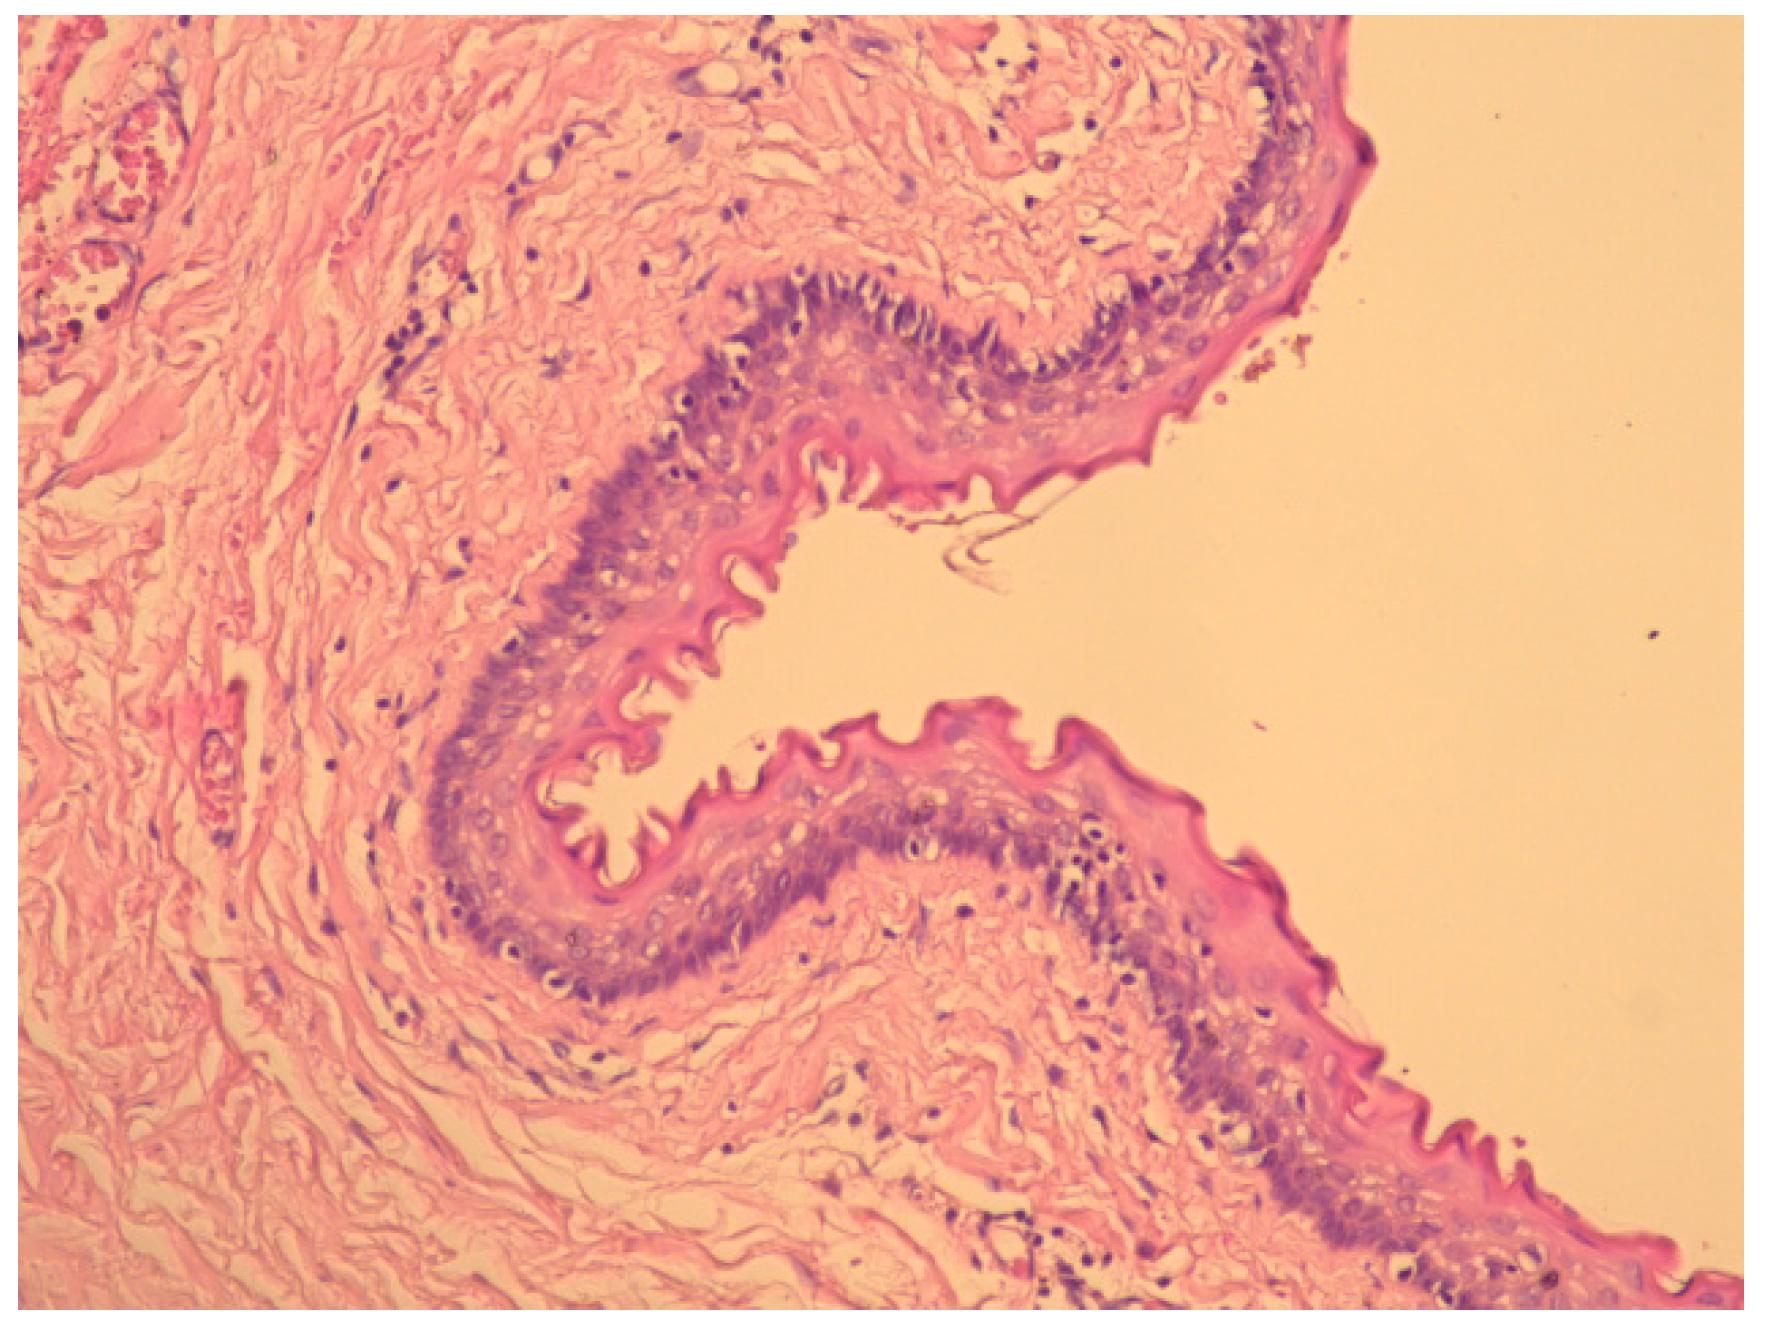

2. Case Presentation